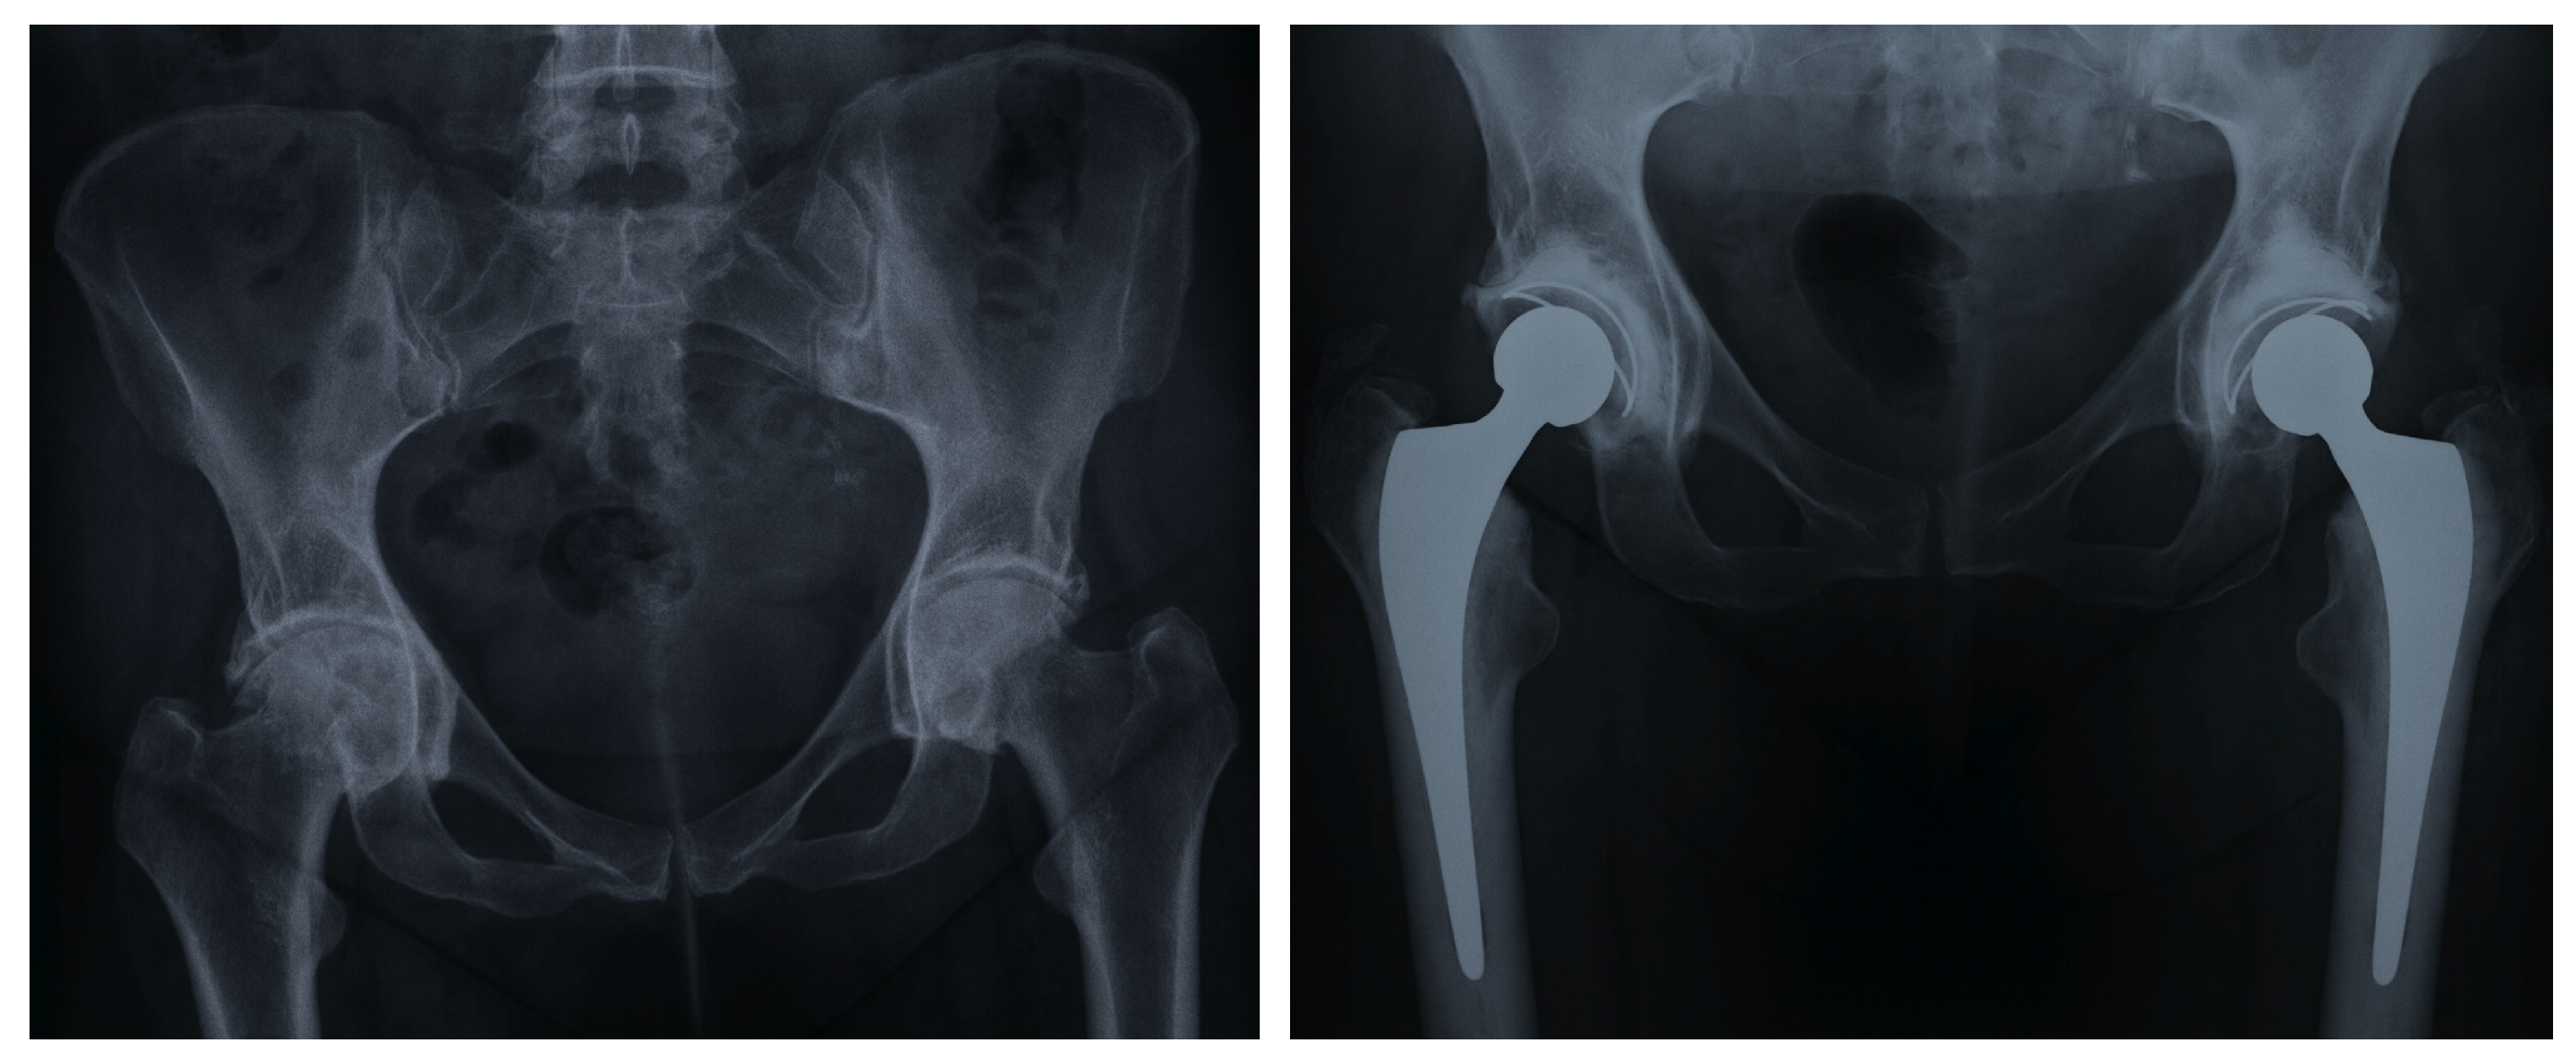

1. Introduction

2. Materials and Methods

2.2. Operative Technique